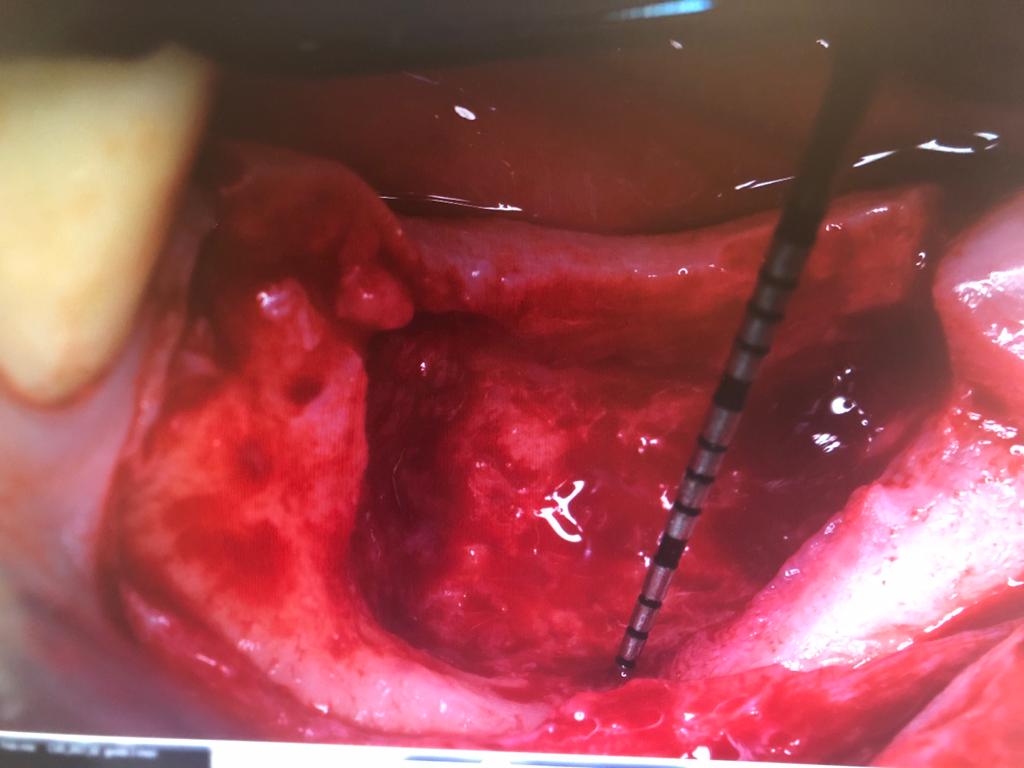

Questa patologia rappresenta una delle cause della perdita di tessuto connettivo, del riassorbimento dell’osso alveolare e della formazione di tasche parodontali che possono condurre alla perdita dei denti ed è una delle cause più comuni della perdita dei denti negli adulti. Grazie alla chirurgia orale per queste tipologie di malattie infiammatorie che colpiscono il tessuto di sostegno del dente, vengono eseguiti dei trattamenti parodontali come il curettage ( ossia il procedimento di rimozione del tartaro o della placca dalla parete orale al di sotto della gengiva) o la levigatura delle radici a cielo aperto, o ancora interventi definiti rigenerativi per l’aumento dello spessore osseo, innesti gengivali, rimozioni di cisti dentali o tumori del cavo orale. Questa tipologia d’intervento consente di ricostruire il tessuto danneggiato o perso e può avvenire in contemporanea all’intervento implantare (rigenerazione ossea perimplantare) o prima di effettuare l’intervento stesso ( rigenerazione ossea preimplantare). La rigenerazione ossea può avvenire in due modi: tramite l’auto trapianto osseo, ossia il prelievo dell’osso da una parte del corpo del paziente e l’innesto nella gengiva, oppure si procede con l’applicazione di osso artificiale, realizzato in materiale sintetico e biocompatibile, che istallato nella gengiva e ricoperto da una membrana riassorbibile, si integra perfettamente con l’osso. Il nostro studio medico dentistico, grazie alla consolidata collaborazione con il dipartimento di parodontologia della facoltà di Odontoiatria dell’Università “La Sapienza “ di Roma e alla comprovata esperienza nel campo implantologico e parodontale è in grado d’intervenire con entrambe le modalità, garantendo al paziente la massima efficienza